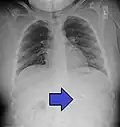

AP X ray showing a 9mm battery in the intestines

Lateral X ray showing a 9mm battery in the intestines